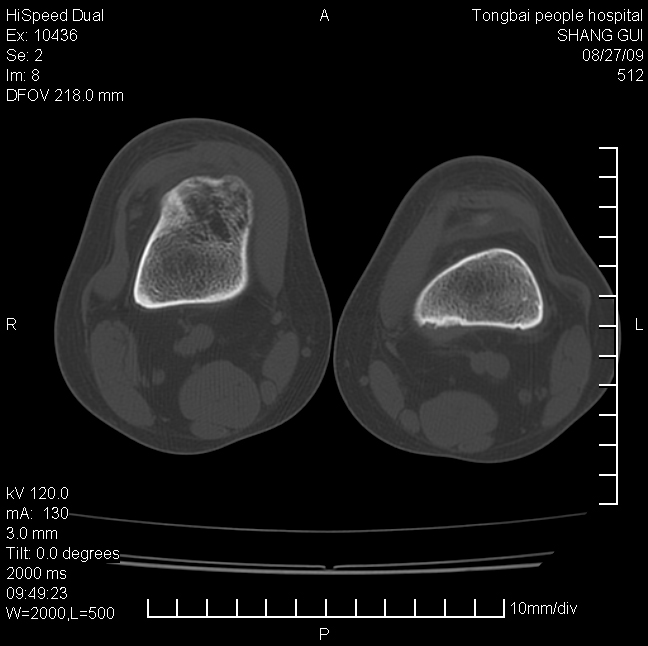

女,12岁。无意发现股骨下端隆起。局部皮肤颜色,温度无异常。

考虑右股骨下端骨纤维结构不良;不排除非骨化性纤维瘤。

不能排除,其实平片更直观。宽基底骨软骨瘤皮质与骨干皮质相连,髓腔与髓腔相通,骨纹理走行方向一致,部分软骨帽可有钙化,本例病变内“磨玻璃状、多囊状改变”比较符合骨纤。